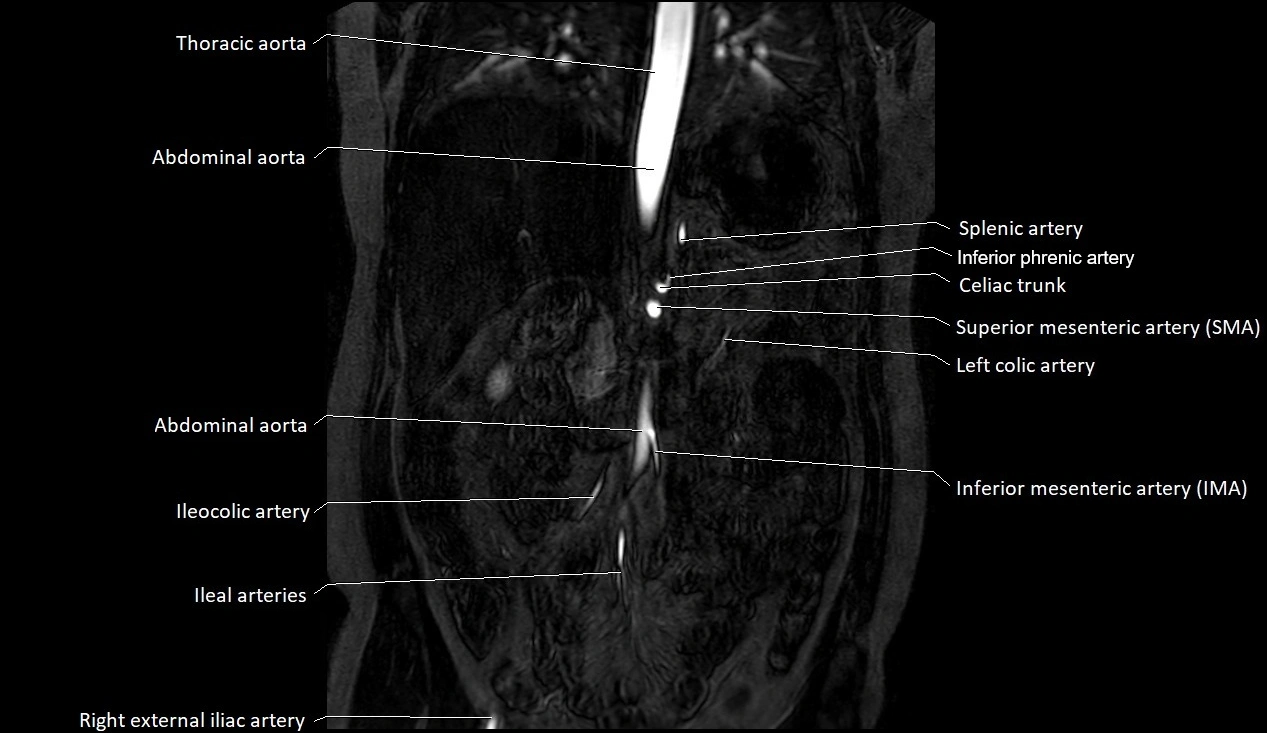

The abdominal aorta is the continuation of the thoracic aorta, beginning at the level of the aortic hiatus of the diaphragm (T12 vertebra) and terminating at the level of the L4 vertebra where it bifurcates into the right and left common iliac arteries. It lies slightly to the left of the midline and courses anterior to the vertebral bodies, surrounded by the retroperitoneal structures of the abdomen.

The abdominal aorta gives off numerous visceral and parietal branches, supplying the abdominal organs, pelvic structures, and lower limbs. It is the main conduit of oxygenated blood from the heart to the abdomen and lower body. The aorta is clinically significant as the common site of aneurysm, dissection, atherosclerosis, and traumatic injury.

Branches

• Unpaired visceral branches: celiac trunk, superior mesenteric artery (SMA), inferior mesenteric artery (IMA)

• Paired visceral branches: middle suprarenal arteries, renal arteries, gonadal arteries (testicular or ovarian)

• Parietal branches: inferior phrenic arteries, lumbar arteries, median sacral artery

• Terminal branches: right and left common iliac arteries

MRA (Magnetic Resonance Angiography):

• Contrast-enhanced MRA provides high-resolution imaging of the aorta and its branches

• Allows 3D reconstruction of visceral, parietal, and terminal branches

• Excellent for evaluating aneurysm size, dissection flap, stenosis, or preoperative planning

• Non-invasive alternative to conventional angiography

MRI images

image